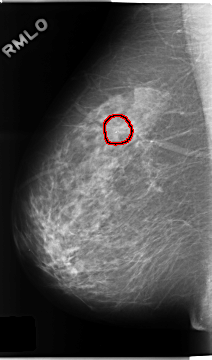

C_0242_1.RIGHT_MLO

RIGHT_MLO LINES 4680 PIXELS_PER_LINE 2744 BITS_PER_PIXEL 12 RESOLUTION 50 OVERLAY

FILE: C_0242_1.RIGHT_MLO.OVERLAY

TOTAL_ABNORMALITIES 1

ABNORMALITY 1

LESION_TYPE CALCIFICATION TYPE PLEOMORPHIC DISTRIBUTION CLUSTERED

ASSESSMENT 4

SUBTLETY 5

PATHOLOGY BENIGN

TOTAL_OUTLINES 1